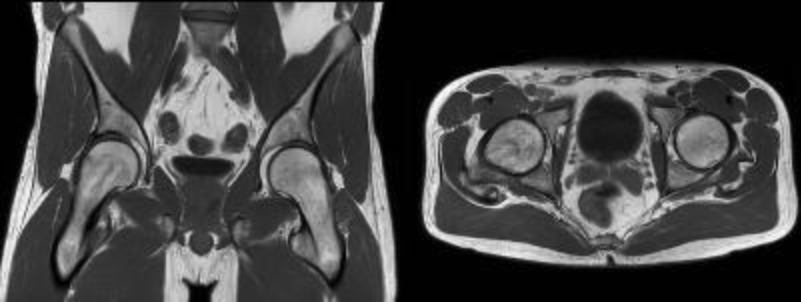

| COR | STIR | YES | YES | Cover Pelvis - Iliac Crest through lesser Trochantors. Skin to Skin A to P. |

| COR | T1 | YES | YES | Cover Pelvis - Iliac Crest through lesser Trochantors. Skin to Skin A to P. |

| AX | T1 | YES | YES | Cover Pelvis - Iliac Crest through lesser Trochantors. Skin to Skin A to P. |

| AX | T2 + fatsat | YES | YES | Cover Pelvis - Iliac Crest through lesser Trochantors. Skin to Skin A to P. |

- You can change the number of slices, TR, FoV, etc. to get scan into a single acquisition.

- DO NOT CHANGE SLICE THICKNESS OR GAP.